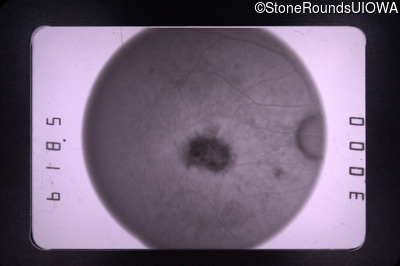

Fluorescein Angiography - Left - 20/400

Exemplar